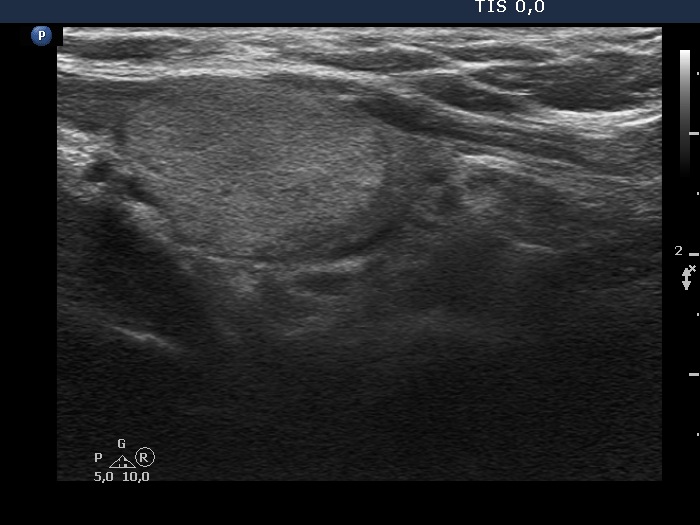

The echogenicity of the nodule - case 2143 (ultrasonographic picture 3)

Right lobe, longitudinal scan.